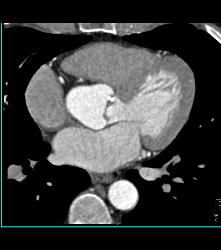

Pseudo-aneurysm Arises Off Aortic Root